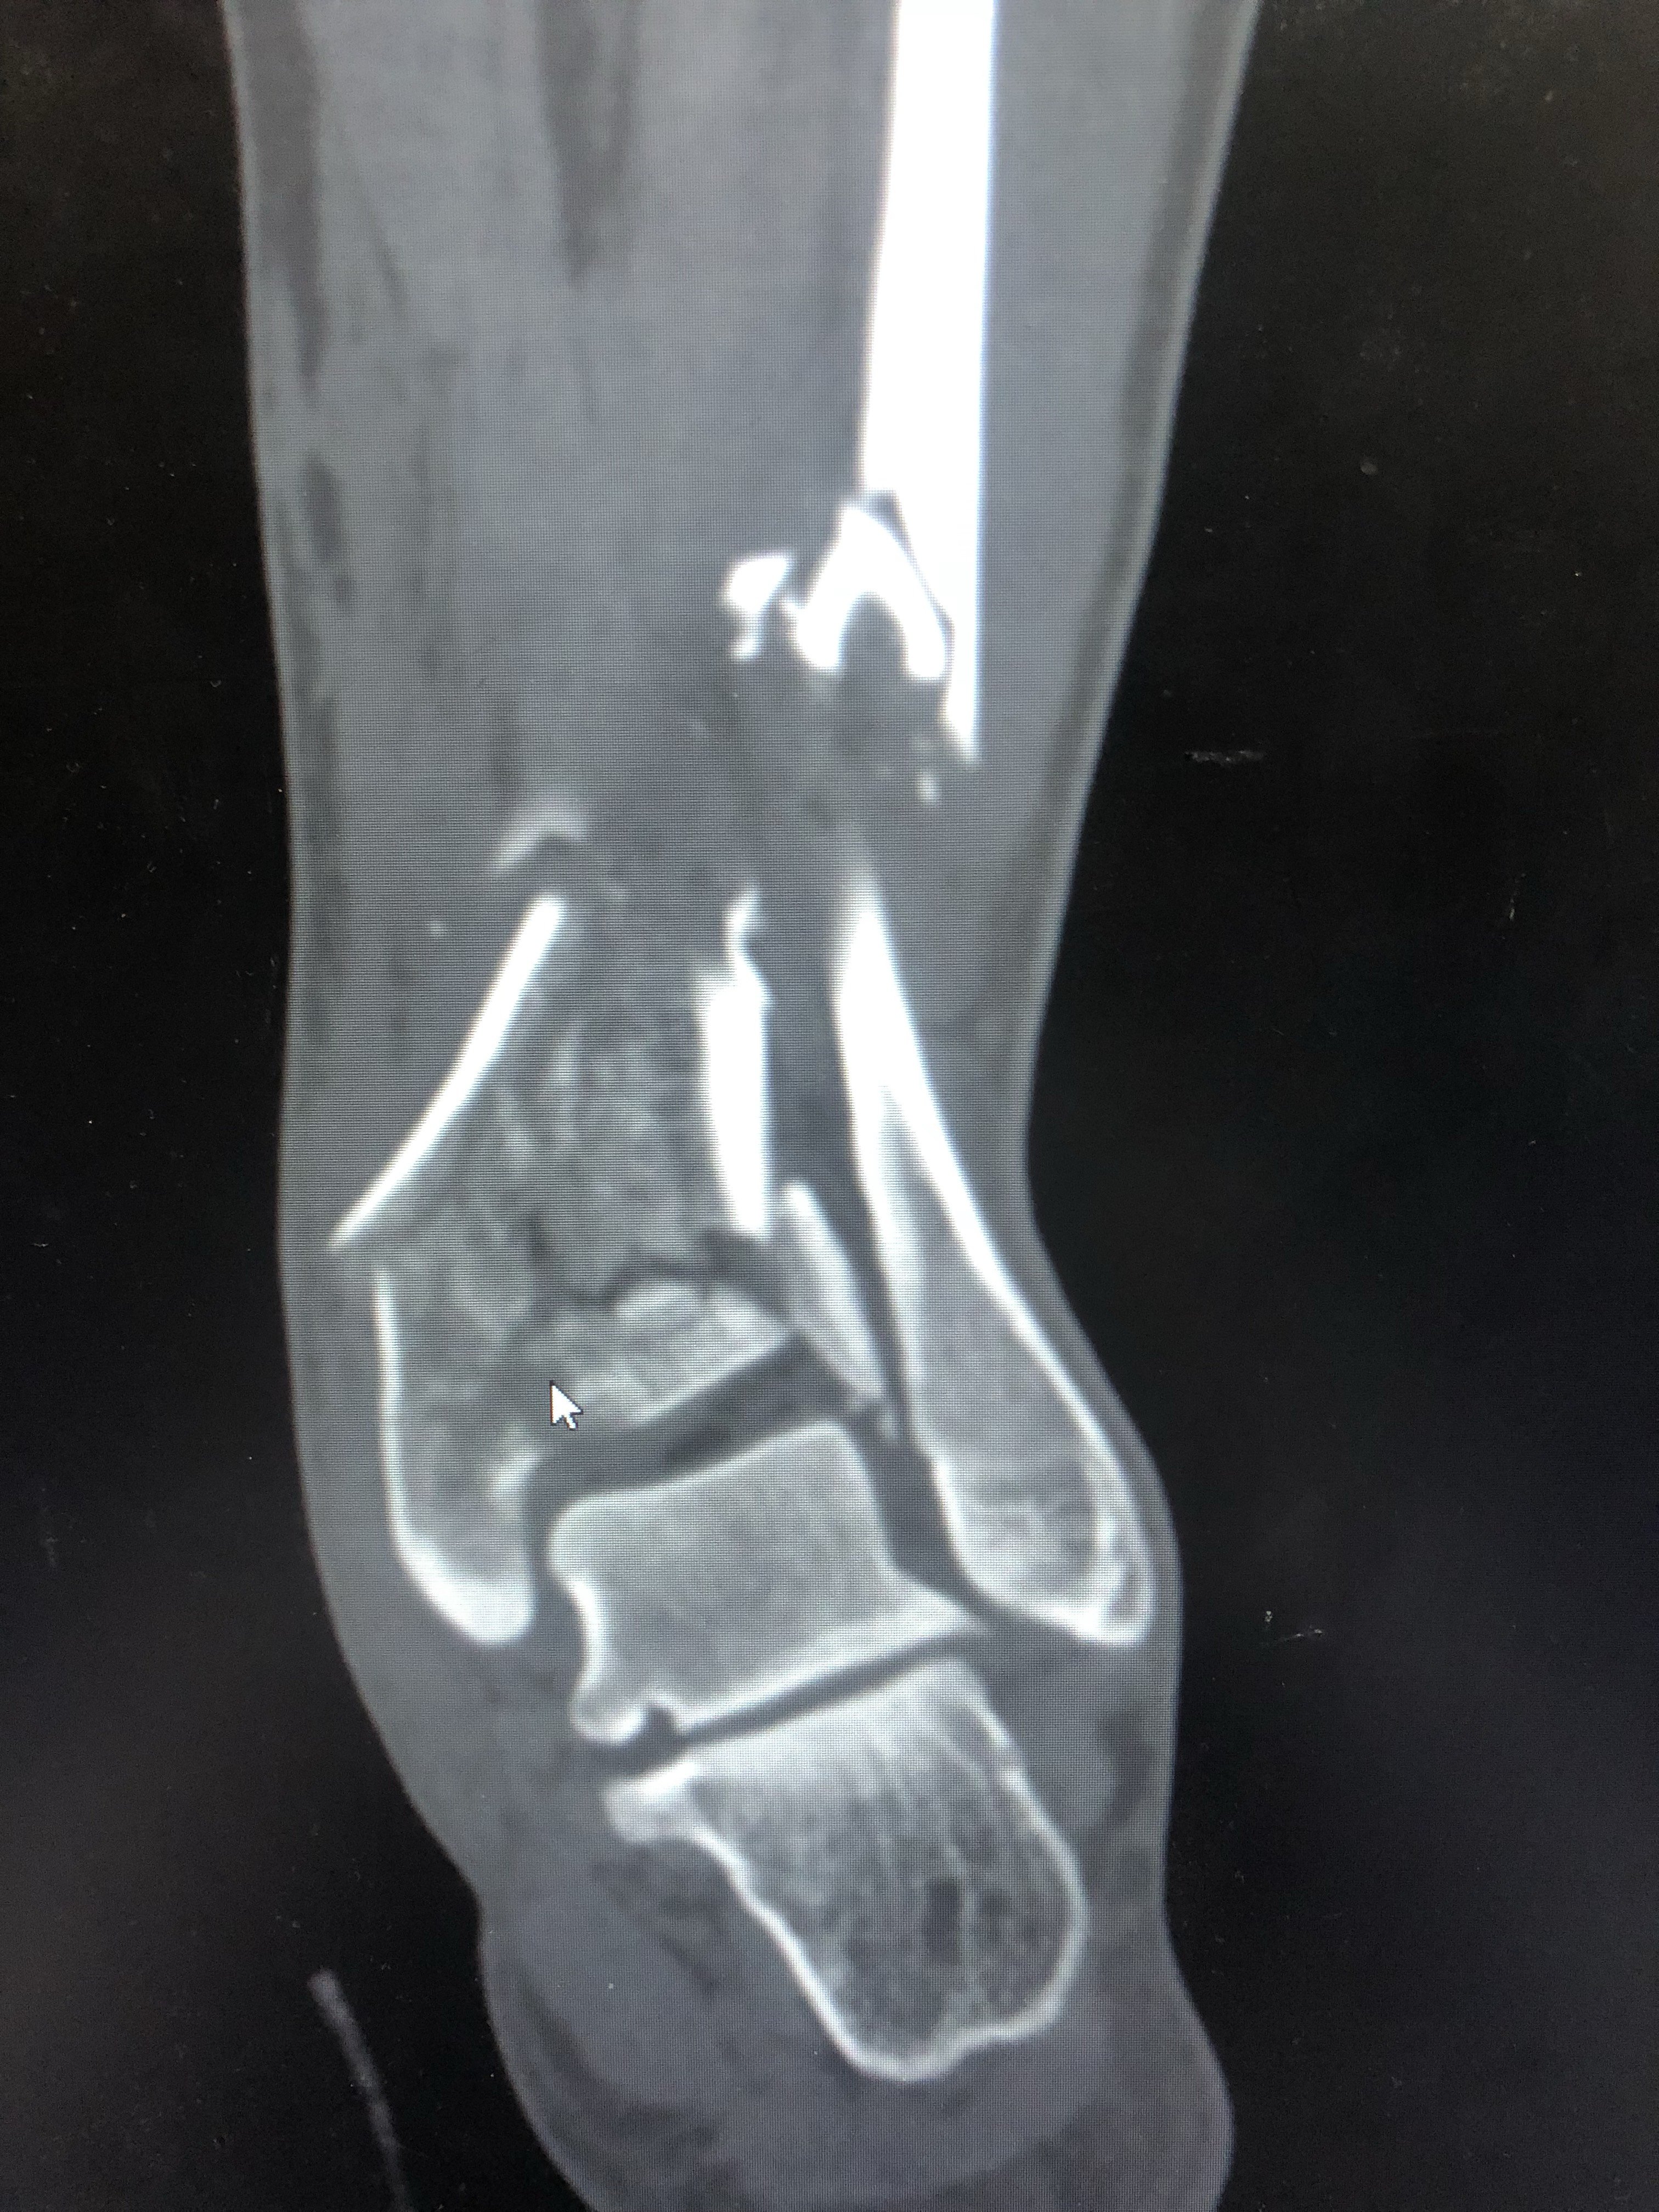

受傷した 画像所見より左腓骨遠位端骨折と診断された前 脛腓靭帯付着部の剥離骨折, 腓骨のらせん骨折および脛骨後 果の骨折からLaugeHansen分類ではSER型stageⅢであった 受傷後9日目にロッキングプレートを用いた骨接合術が施行 された左足首の骨折。 過去に足首を捻挫または骨折をして、治ってからも予防のためにサポーターを着用していませんか? サポーターを着用していると捻挫の予防になるかもしれません。しかし、時に逆効果になってしまう場合もあります。 &n交通事故の被害に遭い、脛骨骨折や腓骨骨折の怪我を。 その後、もしも後遺症が残ってしまったとしたら。 これからも長く続く治療やリハビリの生活では、 脛骨骨折・腓骨骨折から回復するために支払う治療費 怪我をしたことや後遺症が残ったことによる精神的苦痛に対する慰謝料 将来

一例严重的胫腓骨远端粉碎骨折